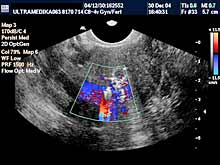

- C) Histerosalpingo kontrast sonografija - metoda koja je u potpunosti

zamenila klasičnu invazivnu rendgensku metodu –HSG. Ova metoda nije

bolna, nema osetljivosti na kontrast a senzitivnost joj je veća nego

klasične metode. Koristi se 3D, i 3D CPA i CD ultrazvučna tehnika.

Ova metoda nam omogućava procenu anatomije i prohodnosti jajovoda.

Ako su jajovodi zapušeni, tj nemoguća je propargacija kontrasta ona

je začeće prirodnim putem nemoguće te se savetuje van telesna

oplodnja.

Preduslovi za adekvatnu UZ dijagnostiku su:

- 2D i 3D Sono CT uz brad

band CD i 3D CPA i CPD sa sondom broad band 5-12MHz.